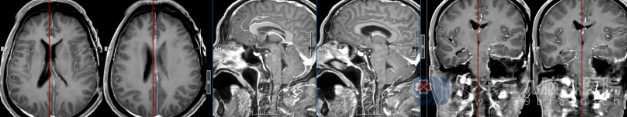

术后头颅MR检查提示:1.左侧桥小脑区占位性病变切除术后改变,术区颅骨内板下及术区少量混合性积液;

在麻醉科团队的保障下,神经外科手术团队在导航引导下,经左侧中后颅窝入路,在高倍显微镜下逐步分离肿瘤与脑干、面神经等重要结构,最终完整切除病变组织,并同期进行了硬脑膜修补与骨瓣成形。

手术历时近8小时,过程顺利。术后患者因病情较重转入重症医学科,经对症支持治疗后病情平稳,转回神经外科继续康复。针对术后出现的肺部感染,医护团队及时调整抗感染方案,并联合康复医学科开展早期康复干预